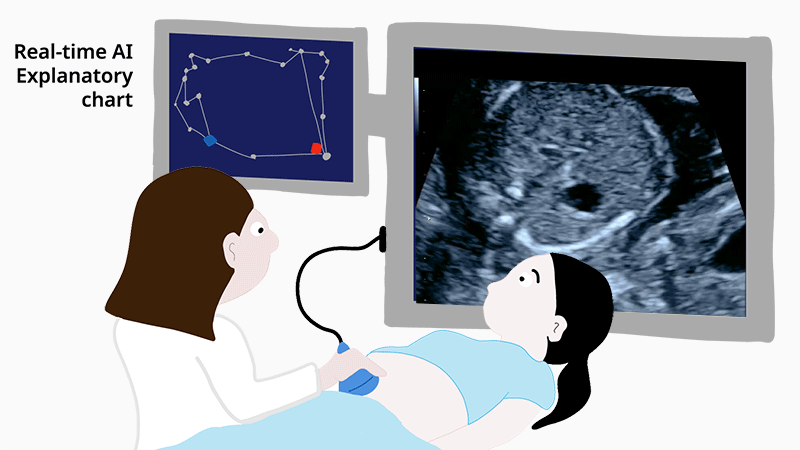

The system has done well in the laboratory, but making it work in a real-world setting brings an entirely new set of challenges. As Komatsu explains, “It’s difficult to build trust with medical professionals when the decisions made by AI take place in a ‘black box’ and cannot be understood.” The new study tested an improved explanatory AI system that allows doctors to view a graphical chart that represents the AI’s decisions. In addition, the charts themselves are generated through another round of deep-learning, which improved AI performance and allowed doctors to see if the abnormalities are related to the heart, blood vessels, or other features.

Experts, fellows, and residents were given the same sets of ultrasound videos and asked to provide diagnoses twice, once without the explanatory AI and once assisted by the graphical representation of the AI’s decision. The examiners were not given the actual AI decision, which is simply a numerical value. The researchers found that each group of doctors made more correct diagnoses when using the new AI-based decision charts. “This is the first demonstration in which examiners at all levels of experience were able to improve their ability to screen ultrasound videos for fetal cardiac abnormalities using explainable AI,” says Komatsu.

Fig 1. Cartoon showing the proposed system. Doctors use explanatory AI to screen ultrasound videos for fetal heart problems. In this study, hospital fellows improved their diagnoses by 7% using the AI-generated graphs.